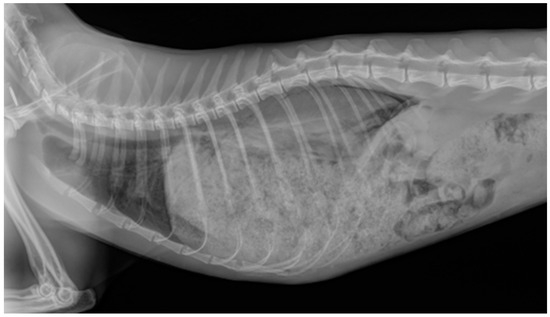

3.4. Results for Cats in Group T—Traumatic Origin